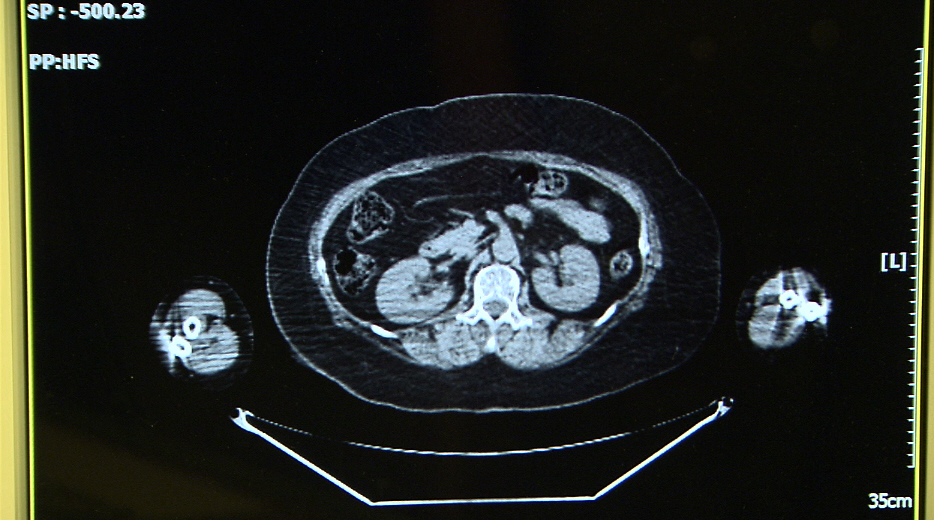

당뇨, 고혈압, 비만을 함께 가지고 있던 36세의 김수정(가명) 씨,

월경이 불규칙하고 임신이 잘 되지 않아 불임클리닉을 다니던 중 우연히,

자궁내막암이 발견되었다.

당시 복부지방이 많았던 그녀는 자궁 주변으로 기름이 많이 껴있고,

심지어 혈관과 임파절 주변까지도 지방으로 뒤덮인 상태였다.